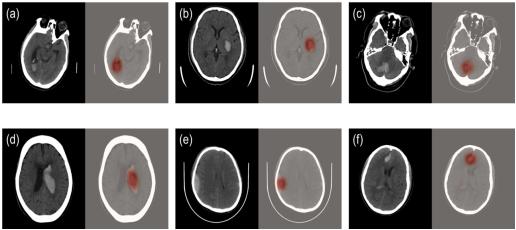

科亚医疗的“CuraRad-ICH”是一款专注于对脑卒中进行快速脑部出血预警的AI影像分析处理软件,可以通过深度学习技术准确、快速地筛查急性脑出血病例,并直接无缝接入医院PACS系统, 自动升高脑出血病例的优先级,提示影像科医生优先完成病患的诊断评估,从而有效缩短脑卒中病患的诊断治疗时间,挽救生命。

在来自全美48个州296家影像中心的临床测试中,CuraRad- ICH分析处理软件达到了91%的敏感性和93%的特异性,同时平均每次预警仅耗时43秒,大幅度缩短出血性脑卒中病患的诊疗时间,受到临床专家的一致认可。